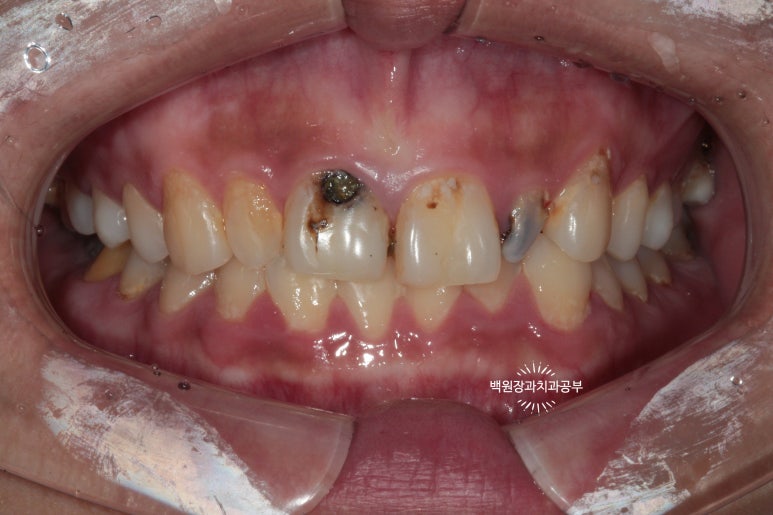

저희 병원을 처음 내원하셨을 때의 구내 임상사진입니다.

20대 여성분이셨는데, 개인 사정으로 적절한 내원 타이밍을 놓쳐 대문니(=중절치)를 비롯하여 상당히 충치가 진행된 양상을 띄고 있습니다. 특히 대문이 옆의 작은 앞니(=측절치)는 충치가 더 심했습니다.

딱 보기에도 치료가 아주 시급해 보이는 상황이었어요!!